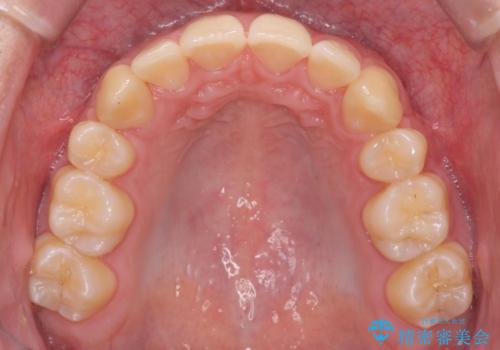

上下の前歯の重なりが大きく(過蓋咬合)時間がかかりましたが、しっかり浅く仕上げることができました。

矯正をしてよかったと大変喜んでおられました。